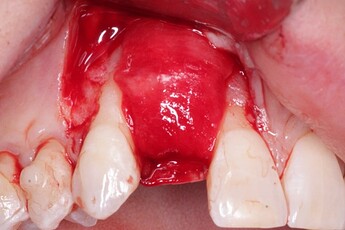

An implant was placed in site #7 with an existing buccal bone defect (Pictures 1 & 2). Prior to placing the bone graft over the implant, the membrane is measured and trimmed and tucked under the palatal flap trying to avoid wetting the entire membrane (Picture 3). The particulate bone graft (DALI Classic Cortical Cancellous Mix) is placed over the implant surface to restore the defect (Picture 4). The membrane is folded over the crest and onto and slightly beyond the particulate bone graft while slowly dropping saline onto the membrane (Picture 5). This enables the membrane to contour and drape over the graft and “seal” the graft off from the surrounding soft tissue (Picture 6 and 7). Sutures are then used to achieve primary closure over the GBR site (Picture 8).

Pic 3

osseoseal-3